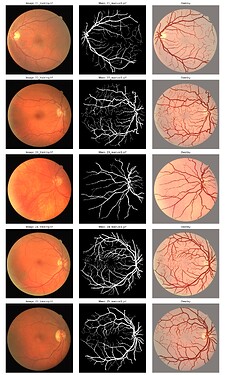

本教案数据来自Kaggle: DRIVE Digital Retinal Images for Vessel Extraction | Kaggle

首先看一下文件夹和图片的格式: